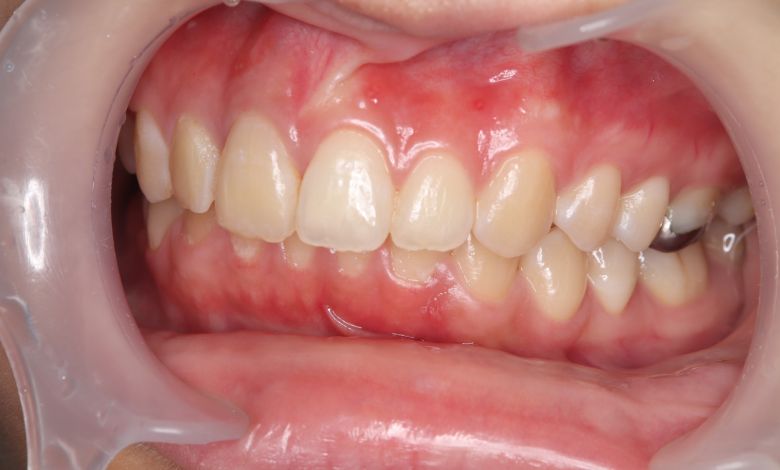

正常な咬合関係が確立され、前歯の自然なアーチと歯軸も整い、歯列全体が滑らかなカーブを描く美しい歯並びに

上下の歯がしっかりと噛み合う、美しい咬合(こうごう)が得られた

精密検査の結果、当院では抜歯を行わず、歯列弓の拡大によってスペースを確保し、非抜歯での矯正治療を選択しました。歯列の叢生(ガタガタ)は解消され、機能的かつ審美的に優れた咬合が得られました。